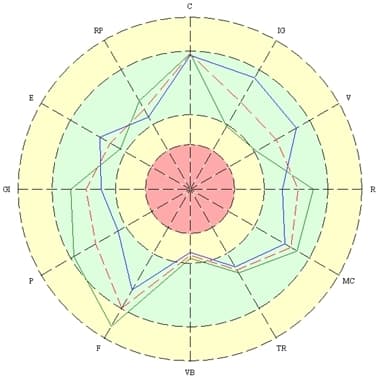

An electroencephalogram is a plot of a recording of the bioelectric activity of the cerebrum in the frequency range from 0.3 to 50 oscillations per second, divided into a number of bands (delta, theta, alpha, beta, gamma). An EEG can be used to evaluate processes occurring in the cerebrum and can be successfully employed in the diagnosis of various diseases and conditions of the central nervous system. The cerebral hemispheres generate radiation independently and may operate in concert or in an uncoordinated way. The cerebral hemispheres differ in their functions. The right hemisphere perceives intuitive, figurative, and abstract information, while the left hemisphere perceives concrete, logical information. For example, the center of speech is located in the left hemisphere. Human evolution is a result of both growth in the capacity of each hemisphere and an increase in the number and quality of interconnections between them. The number of inter-hemisphere connections is a manifestation of the coordination of the two hemispheres. A person is competent in all areas (physical, mental, social) only when the maximum number of interconnections between the hemispheres have developed in the brain and the interactions between them are harmonious and coordinated. The degree of coordination between the interconnections is marked by color in the charts: maximum coordination – pink, average – red, imbalance – dark blue, maximum imbalance – light blue.

We present examples of changes observed in EEG parameters during use of the Aires Defender. We note that in no case was there an worsening of the initial measurements. For convenience, the EEG being compared are placed next to each other. On the left is the initial data. One the right is the baseline of Aires Defender usage.

Figure 1 on the left presents the initial EEG of a 30-year-old test subject before use of the Aires Defender. Complaints were made about poor diligence at the computer due to rapid eye strain, and about a decreased concentration and reduced memory. The “flat” EEG clearly has low-amplitude alpha activity.

On the right is a second EEG, after using the Aires Defender for 30 days. There is a noticeable increase in the alpha rhythm. The test subject mentioned an increase in capacity to work and an improvement in concentration and memory.

It can be seen in Figure 2 that the initial EEG recorded destructive interaction (dark blue) in the delta-1 band and the depletion of intercenter links. After a month of using the Aires Defender, the destructive interactions were eliminated, and the intercenter links in the delta-1 band were restored and concentrated. Ideally, each center should have a coordinated, consonant link (pink or red) with all others, which would increase its functional capabilities and the abilities of the entire system as a whole.

based on cross-correlation in the delta-1 band.

based on cross-correlation in the delta-2 band.

It can be seen in Figure 3 that the initial EEG recorded destructive interaction (dark blue) and the depletion of intercenter links, also in the delta-2 band. After a month of using the Aires Defender, the destructive interactions were eliminated, and the intercenter links in the delta-2 band were restored and concentrated.

Fig. 4 – The depletion of intercenter links was observed in the initial EEG. After a month of using the Aires Defender, the intercenter links in the theta band were restored and concentrated.

based on cross-correlation in the theta band.

based on cross-correlation in the alpha band.

Fig. 5 also shows a depletion of intercenter links in the initial EEG. After a month of using the Aires Defender, the intercenter links in the alpha band were restored and concentrated.

Fig. 6 – Destructive interactions (dark blue) and the depletion of intercenter links were observed in the initial EEG. After a month of using the Aires Defender, the destructive interactions were eliminated, and the intercenter links in all frequency bands were restored and concentrated.

based on cross-correlation in all bands.

Figure 7 shows the phase delays (blue and dark blue) at the different leads before the application of the Aires Defender. This creates a functional asymmetry of the hemispheres. After application of the Aires Defender, symmetry is restored.

In summary, the EEG data presented indicates entirely positive changes in the functional state of the central nervous system with the use of the Aires Defender, in all examined cases.